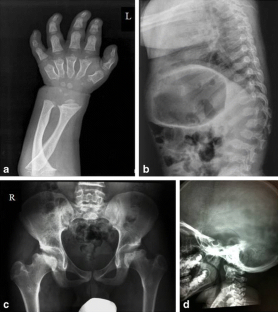

Fig. 1

The authors wish to thank Dr Alberto Gaeta from the Radiology Unit, Pope Giovanni XXIII Pediatric Hospital, Bari, Italy, for contributing the radiographic image of MPS.